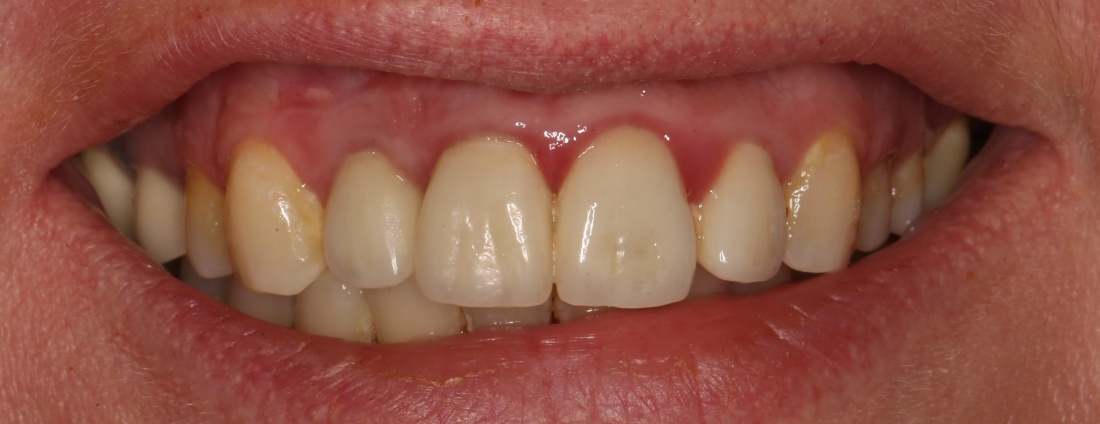

В общем, так и получилось. Уж не помню, почему я наобещал пациентке, что мы поставим ей имплантаты одновременно с остеопластикой. Но я наобещал. И, когда увидел клиническую картину в полости рта:

у меня появились серьезные сомнения, смогу ли я выполнить своё обещание. Вот только не спрашивай меня «Вот чо, сложно было по КЛКТ посмотреть?». Я же не спрашиваю тебя, где ты был в 2013 году, и сделал ли ты домашку. Но, в целом, план операции у нас не поменялся. Как и было оговорено, мы проведем остеопластику с одновременной имплантацией в боковом участке нижней челюсти справа.

Мы встретились как старые друзья. Честно признаюсь, я очень переживал. Я ожидал увидеть какую-нибудь жуть, утраченную кость, периимплантит, разрушенный вхлам протез и всё такое. Но… всё оказалось не так плохо: